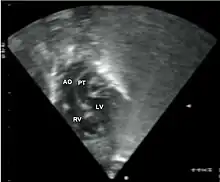

Subcostal echocardiographic view showing discordant ventriculoarterial connections together with the presence of parallel, rather than crossing, great arteries arising from the ventricles.

Transposed vessels can present with atriovenous, ventriculoarterial and/or arteriovenous discordance. The effects may range from a slight change in blood pressure to an interruption in circulation depending on the nature and degree of the misplacement, and on which specific vessels are involved.

Although "transposed" literally means "swapped", many types of TGV involve vessels that are in abnormal positions, while not actually being swapped with each other. The terms TGV and TGA are most commonly used in reference to dextro-TGA – in which the two main arteries are in swapped positions; however, both terms are also commonly used, though to a slightly lesser extent, in reference to levo-TGA – in which both the arteries and the ventricles are swapped; while other defects in this category are almost never referred to by either of these terms.